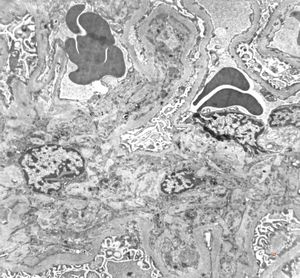

M,6y. | Alport syndrome- digital photo from the screen